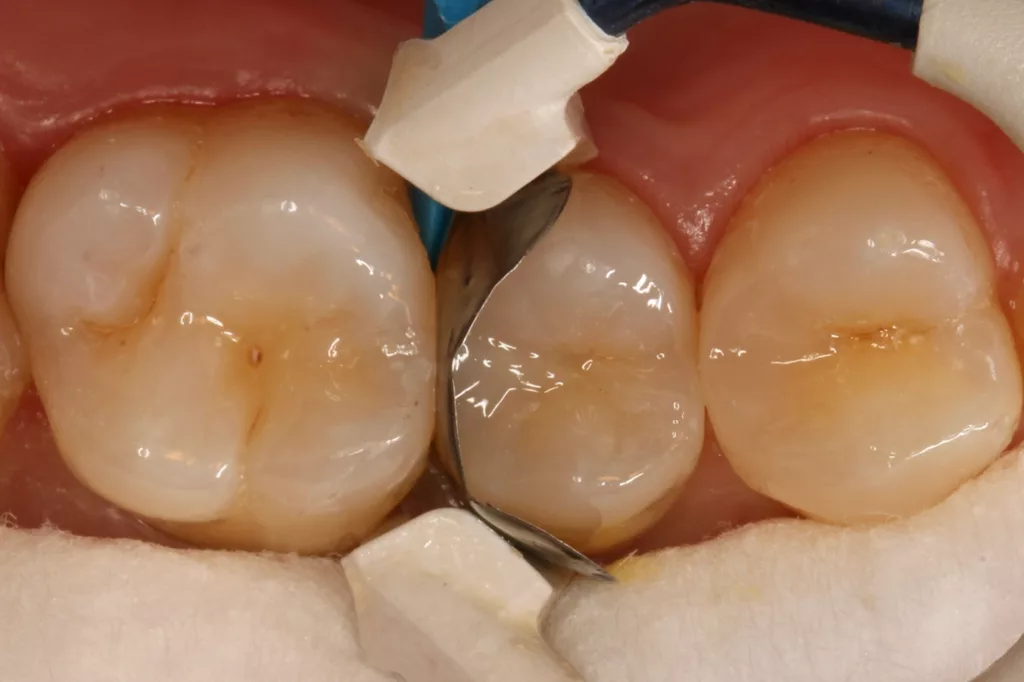

Die 26 Jahre alte Patientin störte sich an der approximalen Lücke zwischen den Zähnen 14 und 15, da sich hier ständig Speisereste impaktierten. Bei der klinischen Inspektion fiel die Initialkaries distal an Zahn 14 auf (Abb. 7). Die Patientin wurde dahingehend beraten, den Spalt mit einer minimalinvasiven Kompositrestauration zu versorgen – bei zeitgleicher Exkavation der Karies an Zahn 14. Nach Exkavation und Präparation des Defektes (der sich als deutlich ausgeprägter präsentierte als anfangs angenommen) erfolgte identisch zu Fall 2 die Ausformung der Kavität mit einer Teilmatrize (Danville ultra thin flex), einem Kunststoffkeilchen (G-Wedge) und der Separation mit einem NiTin-Prämolaren-Spannring (re-invent, Abb. 8).

Teilmatrizensysteme stellen heutzutage die erste Wahl in der Gestaltung anatomischer Kontaktflächen dar [22]: Sie garantieren korrekte anatomische Formen, straffe Approximalkontakte und belastungsoptimiert ausgeformte Randleisten [74–76]. Nach der adhäsiven Vorbehandlung (G2 Universal, GC, total etch) wurde der Defekt identisch zum vorherigen Fall mit dem niedrigviskösen Visalys Bulkflow in einem Zug aufgefüllt und mit der Sondenspitze ausmodelliert (Abb. 9). Die Aushärtung (Elipar Deep Cure) erfolgte erneut standardisiert für jeweils 20 Sek.: einmal okklusal zentral nach Einbringen des Bulkflow-Materials und je einmal als Nachhärtung nach Abnahme der Matrizen-Verschalung aus bukkaler und erneut okklusaler Richtung mit genau auf der Randleiste positioniertem Lichtgerät. So wird mit Sicherheit eine suffiziente Aushärtung des 4 mm tiefen Defektes gewährleistet.